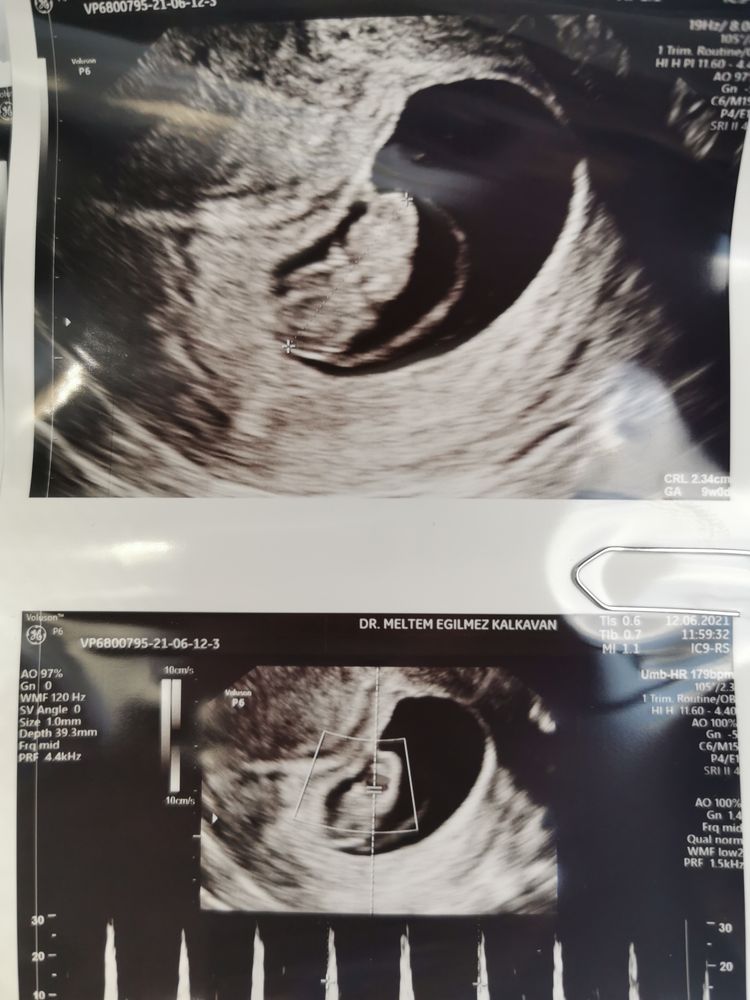

9 недель

Все ровно по сроку. Лежит такой человечек. Ручки, ножки, голова, позвоночник❤️

Сердечко 180 ударов❤️❤️❤️